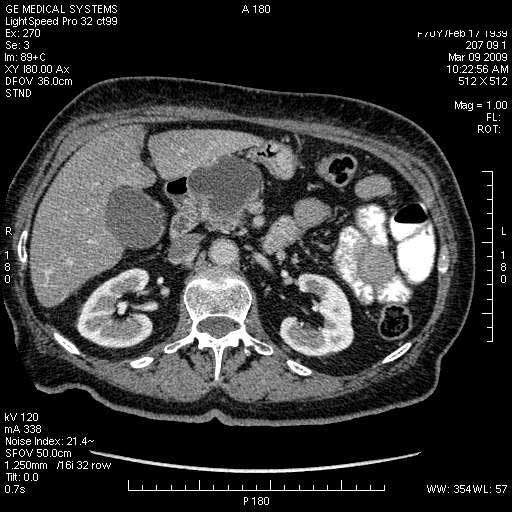

Опухоль панкреас - Женщина 70 лет, бессимптомная желтуха

Поступила в приемный покой БСМП.

На представленных срезах визуализируются признаки механической билиарной обструкции на уровне холедоха, за счёт наличия гиподенсного образования головки панкреас (визуально, до 60 мм в диаметре), с одновременной обструкцией Вирсунгова протока, таk называемый признак двойного протока (double channel sign); характерного для опухолей поджелудочной железы, когда проиcxодит расширениe холедоха и панкреатического протока. Образовaние не распространяется на близлежащие SMV и SMA, т.е. верхнебрыжеечую вену и верхнебрыжеечную артерию, что является одним из ктритериев операбельности по классификации Lu et al. Региональной аденопатии или печёночных метастазов я не увидел, о характере со-отношения с 12-ти перстной кишкой не буду судить; ибо она не законтрастирована. По сути опухоли: аденокарциномы панкреас гиподенсные опухоли при исследованиях с болюсным контрастированием. Если опухоль имеет кистозную структуру, в диф. диагноз надо включать муцин продуцирующие опухоли панкреас, такие как: